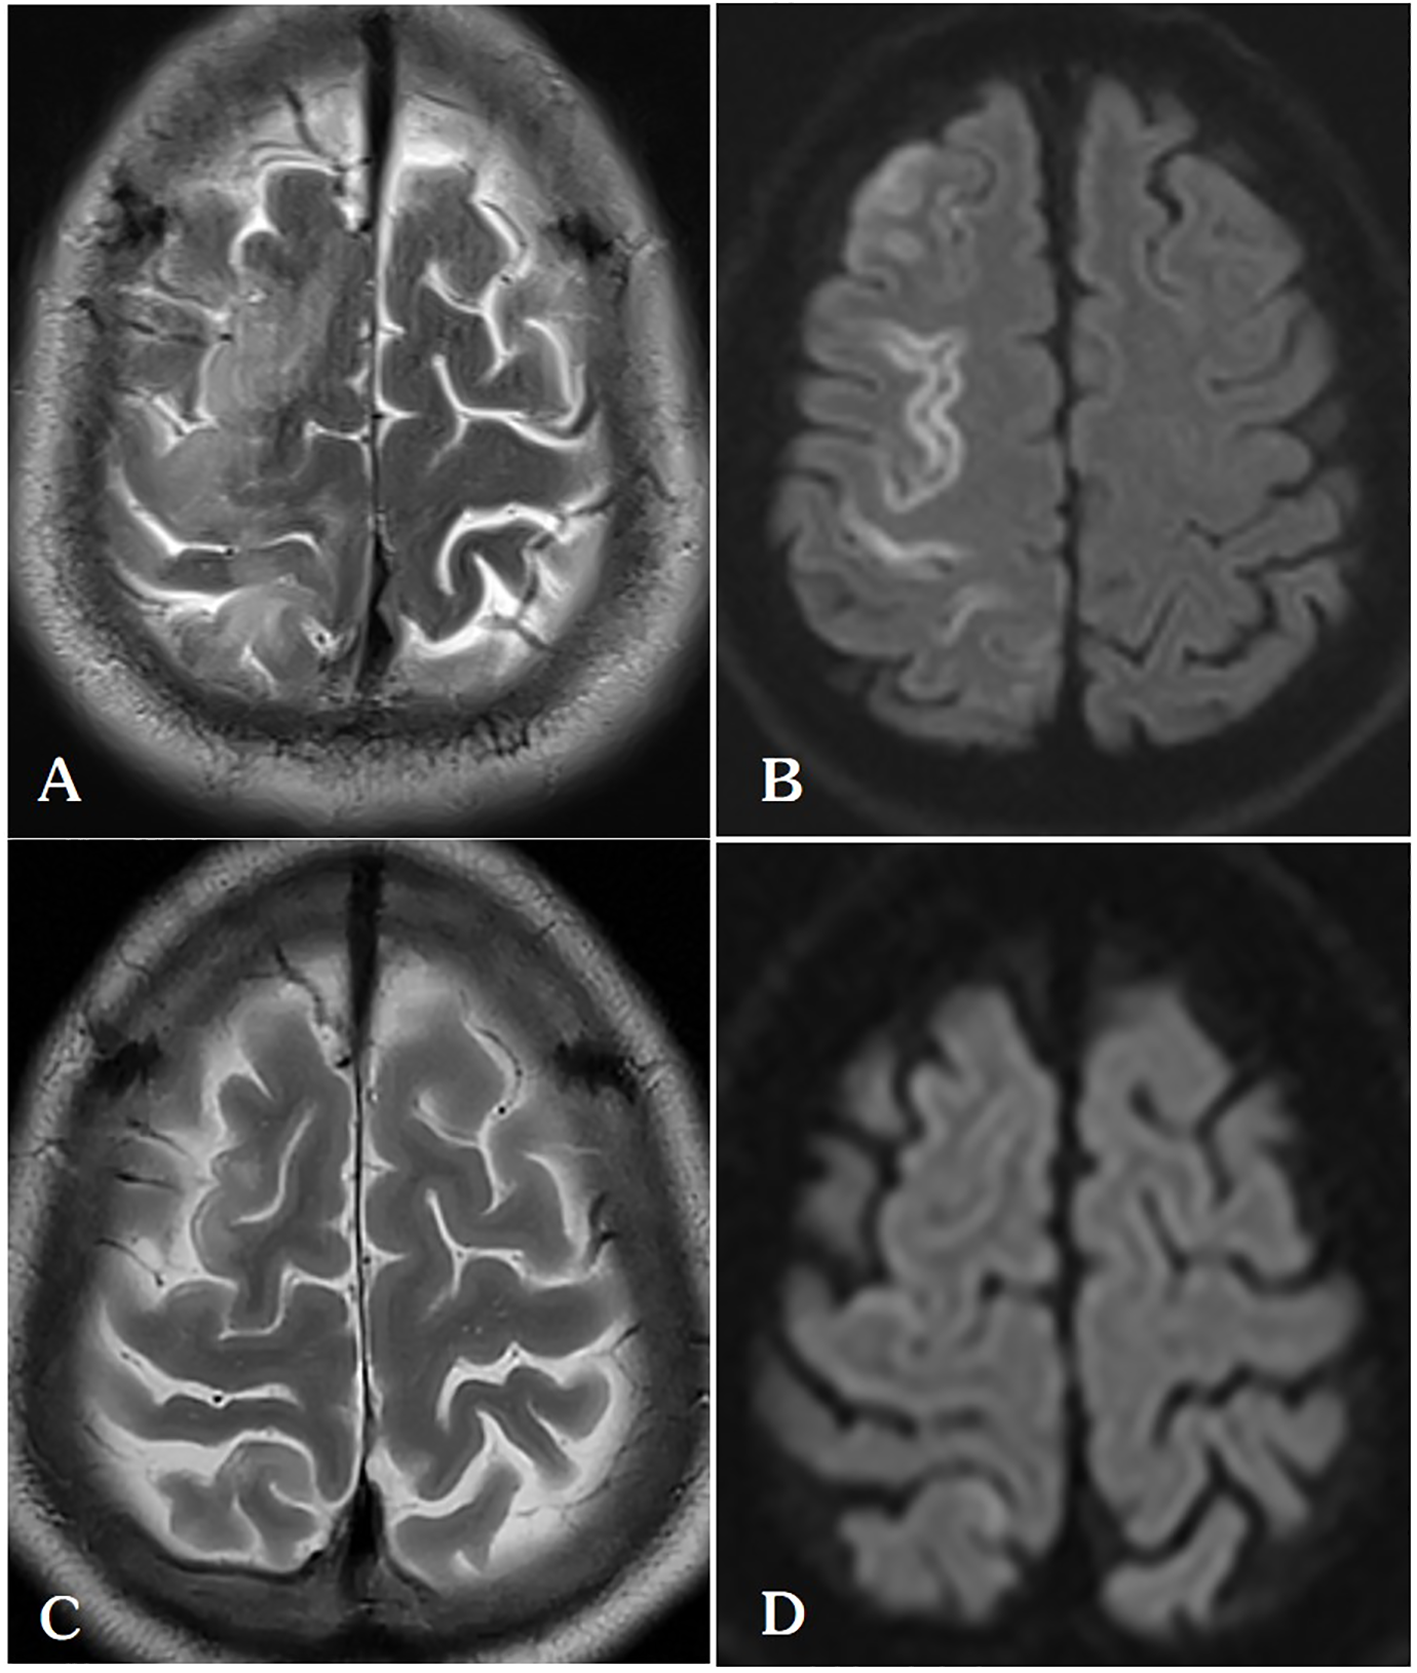

Figure 4

(A, B) On the 5th day after lung ablation, the patient’s head MRI indicated venous infarction in the right parietal lobe. (C, D) After treatment with anticoagulation, scavenging of oxygen free radicals, and neurotrophic therapy, the patient’s follow-up head MRI on the 30th postoperative day showed a significant reduction in the extent of cerebral infarction in the right frontal lobe.

In the neurology ward, the patient was administered oxygen at a rate of 6 L/min via a nasal catheter, which is the standard treatment for pneumothorax. His SpO2 remained stable, exceeding 95%. He received Aspirin (antiplatelet), Edaravone (to protect neuronal cells), and Butylphthalide (improving the cerebral blood circulation), along with bedside rehabilitation. Our hospital does not have the necessary infrastructure for hyperbaric oxygen therapy, and the patient’s family declined our recommendation to seek this treatment at an alternative facility. Over time, the muscle strength in patient’s left limb gradually returned to normal, and follow-up head MRI conducted about four weeks later showed a significant reduction in the extent of cerebral infarction compared to previous scans (Figures 4C, D). The patient was discharged 33 days after the event, exhibiting no neurological deficits (Table 1).